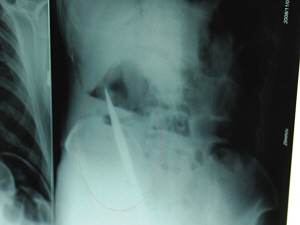

X光片上,尖刀清晰可見。

從男子體內(nèi)取出的尖刀足足有19厘米長。

6日上午,記者在徐州礦務(wù)集團(tuán)總醫(yī)院重癥監(jiān)護(hù)室見到了這名男子,目前他雖然已經(jīng)恢復(fù)了意識,但還不能開口說話,需要呼吸機(jī)輔助呼吸。據(jù)醫(yī)生介紹,4日中午12時左右,這名男子因服毒輕生被緊急送到醫(yī)院進(jìn)行搶救,之前,這名男子已經(jīng)在當(dāng)?shù)剜l(xiāng)鎮(zhèn)醫(yī)院進(jìn)行了近20小時的治療,但效果不佳。“病人被轉(zhuǎn)院到礦總院時已神志不清,血壓極低,處于休克狀態(tài)!本茸o(hù)人員給男子洗胃、初步處理以后,發(fā)現(xiàn)男子呼吸急促,于是趕緊給他拍片檢查。結(jié)果讓所有的醫(yī)生大吃一驚,竟有一把尖狀異物橫在該男子腹腔內(nèi)!當(dāng)天下午5時30分,輕生男子被推上了手術(shù)臺。經(jīng)過40多分鐘的手術(shù),該男子腹腔被打開,手術(shù)醫(yī)生發(fā)現(xiàn),男子體內(nèi)的金屬狀異物竟然是一把長19厘米的尖刀!